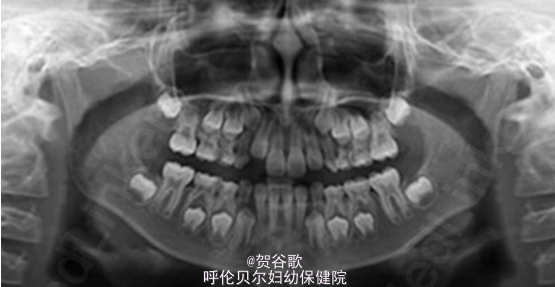

口腔检查:混合牙列 前牙反覆盖,尖牙磨牙III类关系,下颌中线右偏1-2mm 面部外观下颌前突,面下1/3高度正常,面部左右对称 颞下颌关节无弹响,无压痛,开口型开口度正常 拍摄头颅侧位片和曲面断层片

诊断:安氏III类错合 患儿进行了口腔正位片、全景片检查,取模型、诊断、分析设计方案等步骤后,主诊医生表示患儿非常适合利用Frank Ⅲ型功能矫治器治疗,矫治前牙反合,促进上颌骨发育,限制下颌骨发育的功能特点来解除反颌问题。